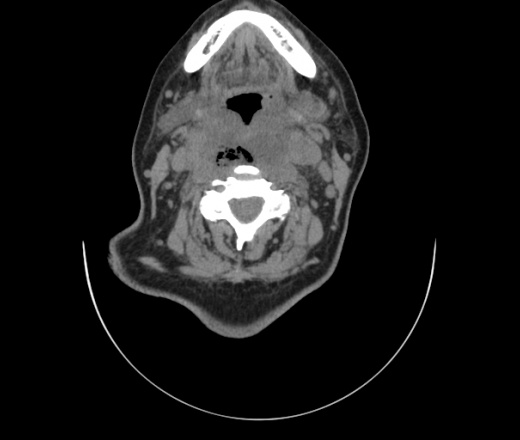

Женщина поступила в х/о спустя 4 дня после того как при употреблении карася подавилась костью.

Наличие газа в средостении на протяжении тел С2-С6 (медиастинальна эмфизема); рыбная кость на уровне тела С6.

При всем уважении, но говорить о медиастинальной эмфиземе, оценивая мягкие ткани шеи, как-то слишком резко. На мой взгляд, это ретрофарингеальное пространство.

Эвакуировали почти 100мл гноя. Но кость не смогли найти. Думаю что она даст дальнейшее ослоднение. Эндоскопически за черпалонадгортаной звязкой не смогли зайти в пищевод, все мягкие ткани отечные, просвет пищевода сдавлен. По всей видимости параэзофагеальная клетчака тоже задействована. Эмпиема, если ее можно так назвать, незнаю как правильно дошла до уровня яремной вырезки. Чем закончиться напишу. Ждем медиастинита.

Флегмона заглоточного пространства шеи, только операция, флегмоны вскрывают. Риск медиастинита.

Согласен с Вами; конечно, наличие газа в клетчатке ретрофарингеального пространства (затмение с опечаткой..). К сожалению, процесс "продвигается" к медиастиниту. Но почему никто, не отмечает наличие рыб. кости; или это для Всех очевидно?

Так вы уже отметили. Хотя ориентировал бы не скелетотопически, а на перстнечерпаловидный сустав.

Кость то мы сразу выявили, размеры где то 17*2мм, но ее так и не получается найти в этой каше